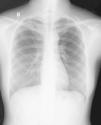

Saturation was maintained at approximately 99% with the oxygen cannula at 2L/min. Physical examination showed palpable subcutaneous emphysema involving the submandibular region, anterior and lateral aspect of the neck, as well as the bilateral supraclavicular regions. There were minor inflammatory signs but there was no local dental infection. Chest radiograph showed pneumomediastinum and subcutaneous emphysema in the neck region (Fig. 1). A computed tomography scan was performed that showed: emphysema extending from the mandibular region to the mediastinum (Fig. 2A and B), as well as the presence of pneumopericardium and left side pneumothorax (Fig. 3A and B) The laboratory tests showed slightly elevated white counts 12400/μL without shift-to-left. The band form was 4% and the segmented form was 80% of total leukocytes. C-reactive protein was 7.4mg/dL. After treatment with a second-generation cephalosporin administered intravenously along with oxygen and oral non-steroid anti-inflammatory drug, the fever subsided within 24h after admission and the symptoms resolved. The patient was discharged 4 days later. After discharge, the patient took oral first-generation cephalosporin for an additional five days. She had a complete clinical and radiological recovery without recurrence of disease (Fig. 4).